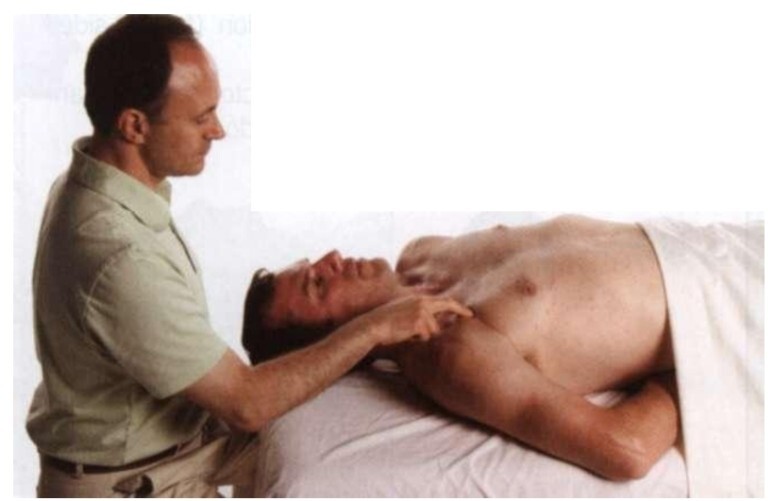

<촉진 단계>

· 환자에게 손과 전완으로 베드를 아래를 향하여 누르도록 지시하고, 대흉근/큰가슴근을 통하여 소흉근/작은가슴근의 수축을 느낀다.

· 계속해서 갈비뼈 부착부위까지 근섬유의 수직방향으로 촉진한다.

· 소흉근/작은가슴근 촉진을 완료시 환자에게 편안한 자세를 취하게하고 기본톤(baseline tone)을 평가하고 촉진한다.

★★★

· 환자가 베드를 손과 전완으로 아래를 향하여 누르는 이유는 팔의 폄(extension)을 유발시키며 이는 짝운동(coupled motion)인 어깨뼈의 아래쪽 돌림(downward rotation)을 유발시켜 소흉근/작은가슴근의 근수축을 유발시킬 수 있다.

소흉근/작은가슴근 수축을 유발할 때는 앉은자세가 제일 쉽다.

· 소흉근/작은가슴근의 세 섬유는 충분히 개별적으로 촉진하고 구분할 수 있다.